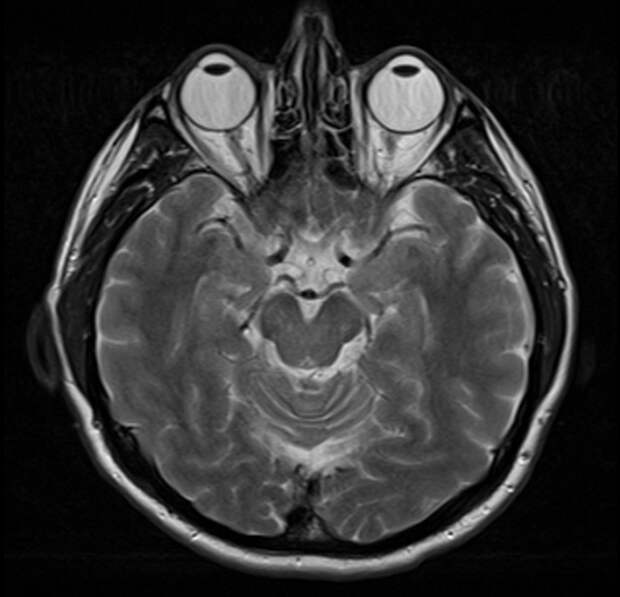

3. МРТ-снимок здорового головного мозга человека